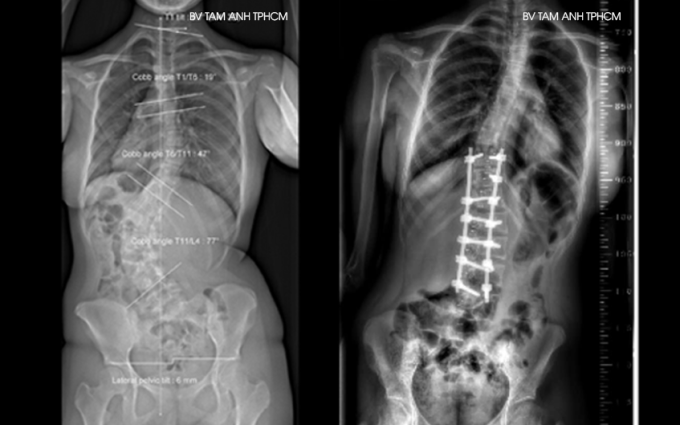

Kết quả chụp X-quang tại Bệnh viện Đa khoa Tâm Anh TP HCM gần đây cho thấy cột sống của An có hai vùng biến dạng, vùng ngực vẹo sang phải 47 độ và vùng thắt lưng vẹo sang trái 77 độ, thắt lưng xoay nhiều. Người bệnh bị lệch vai, lưng biến dạng đến mức có thể nhận ra bằng mắt thường và đau nhiều khi ngồi.

An được phẫu thuật nắn chỉnh cột sống lối sau. Phương pháp này phù hợp với trường hợp vẹo nặng và phức tạp, giúp chống xoay, kéo dài và ổn định cột sống theo cả ba chiều không gian. Bác sĩ mở một đường dài sau lưng, bộc lộ các vùng cột sống bị biến dạng cong vẹo. Sau đó đặt các vít chân cung vào các đốt sống bị biến dạng xoay ở vùng cong vẹo, nắn chỉnh các đốt sống và nối chúng lại với nhau bằng thanh kim loại nhằm cố định cột sống vùng vẹo sau khi nắn chỉnh.